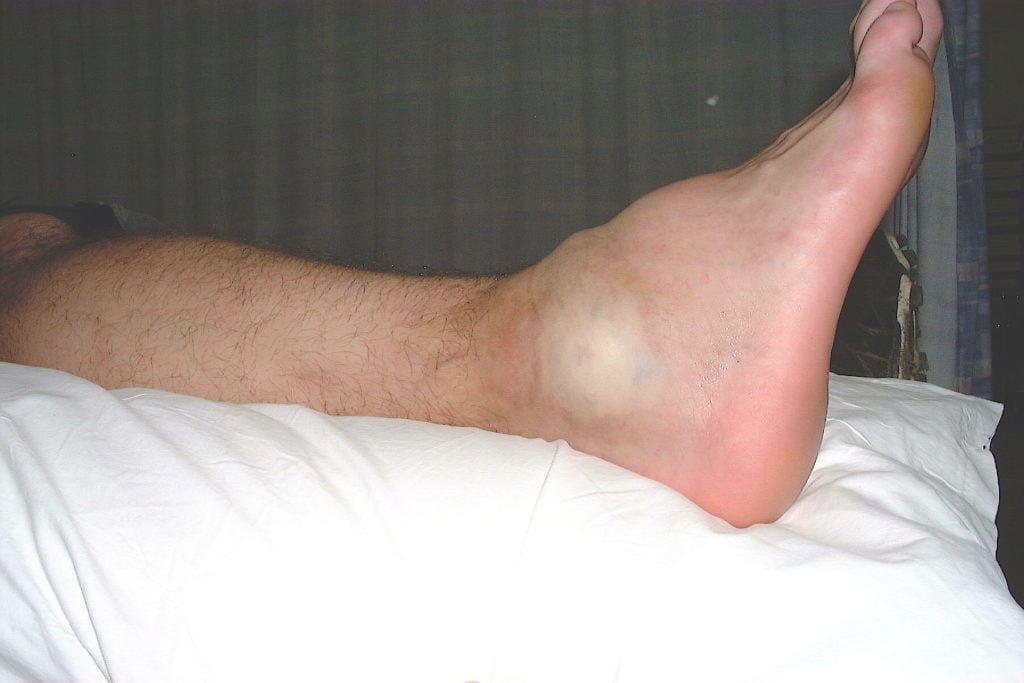

Хруст в голеностопе может быть симптомом практически любой воспалительной или дистрофически-дегенеративной патологии. Если он возникает на фоне болей, утренней скованности движений и припухлости сустава, то причиной крепитации стала деструкция костных, хрящевых или мягких тканей. Оттягивать визит к врачу нецелесообразно, так как все заболевания опорно-двигательного аппарата поддаются консервативному лечению только на начальной стадии. Что еще указывает на развивающуюся в голеностопе патологию:

- синовита — воспаления синовиальной оболочки, распространяющегося на расположенные поблизости соединительнотканные структуры;

- бурсита — воспаления синовиальной сумки, которое сопровождается накоплением патологического экссудата в ее полости.